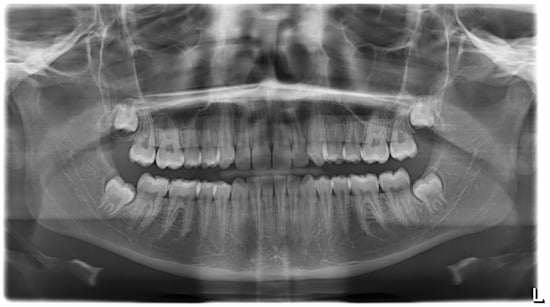

3.1. Clinical Case #1